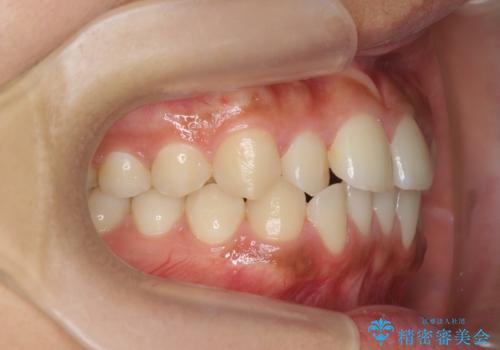

前歯のねじれ、すれ違いを改善 部分ワイヤー+マウスピース矯正

- 上下前歯のすれ違い、ねじれのある歯並びの矯正治療を求めて来院されました。

前歯のすれ違いが改善することで噛みやすくなった。と矯正治療の結果に満足いただくことができました。